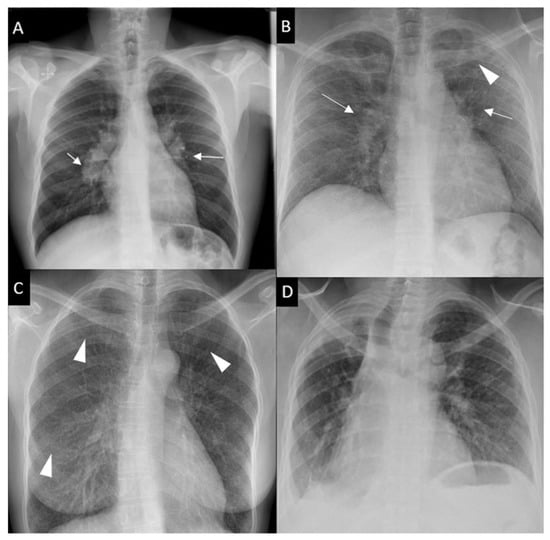

Respiratory symptoms are found at presentation in 30–53% of patients; cough in 27–53%, dyspnea in 18–51% and chest pain in 9–23% [16,30,31]. Chronic dyspnea is most frequently seen in patients with a delayed diagnosis, such as in the 10% of patients diagnosed with sarcoidosis-related lung fibrosis [9]. Bilateral perihilar lymphadenopathy, which is most frequently mediastinal lymphadenopathy [32] and perilymphatic pulmonary nodules predominantly seen in the upper lobe are the most typical imaging findings. Scadding’s classification defines five stages of sarcoidosis on a CXR (Figure 1).

Figure 1. Chest x-ray (CXR) staging system. Stage 0-normal CXR (not shown); (A) Stage 1-bilateral hilar lymphadenopathy (white arrows); (B) Stage 2-bilateral hilar lymphadenopathy (white arrows) and pulmonary infiltrates in upper lobes (white arrowhead); (C) Stage 3-pulmonary infiltrates (white arrowhead) without bilateral hilar lymphadenopathy; (D) Stage 4-pulmonary fibrosis.

This system was developed prior to computed tomography (CT) and is widely used for its prognostic value. Mediastinal lymphadenopathy, especially right paratracheal and aorto-pulmonary locations, are commonly observed on chest CT. Calcifications [33] of lymph nodes may occur in sarcoidosis; they are usually chalky, focal and tend to be bilateral when present [33]. Chest CT is much more sensitive than CXR for the detection of lung nodules and subtle fibrosis. Pulmonary nodules tend to be tiny, usually termed “micronodules” ranging from 2 to 5 mm, typically located along the bronchovascular bundles, interlobular septa, interlobar fissures and subpleural regions, which constitute the “perilymphatic distribution (Figure 2A). Pulmonary fibrotic changes may be a dominant feature with typical features of architectural distortion, volume loss and bronchiectasis, which tend to predominate in the middle and upper lung zones (Figure 2B). Recently, the “dark lymph node” or the “cluster of black pearls” sign (defined by tiny round nodules each measuring 1–2 mm which are seen uniformly distributed throughout all or part of the lymph node) has been described as relatively specific of sarcoidosis with negative and positive predictive values of 96 and 91%, respectively [34]. The “galaxy” sign is also highly suggestive for sarcoidosis; it consists of a large nodule, usually with irregular boundaries, surrounded by a border of tiny satellite nodules. Alveolar, pseudo-alveolar consolidations, or diffuse ground glass are rarely the cause of sarcoidosis-associated radiological abnormalities [35].